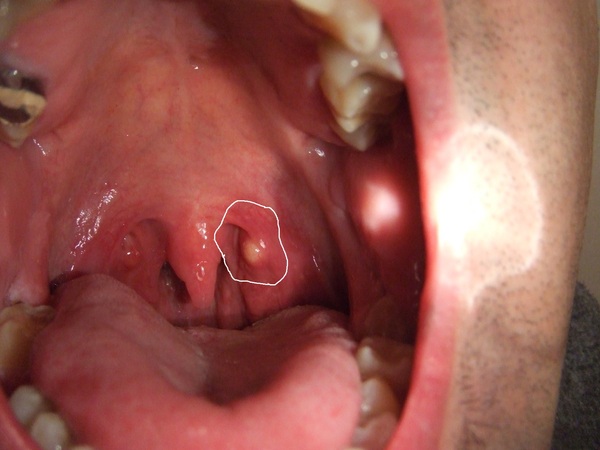

Soft Palate Bumps – Doctor insights on HealthTap